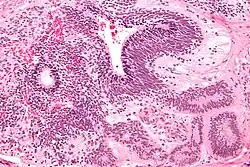

A micrograph showing a choriocarcinoma spread to the lung

Choriocarcinomas are exceptionally rare which account for 2.1%-3.4% of all OGCTs.[10] Under gross examination, the syncytiotrophoblast cells are aligned in a plexiform arrangement with the mononucleated cytotrophoblast cells surrounding the foci of the hemorrhage.[1] Choriocarcinomas can be divided into gestational choriocarcinomas and non-gestational choriocarcinomas which have immunohistochemical differences.[11]